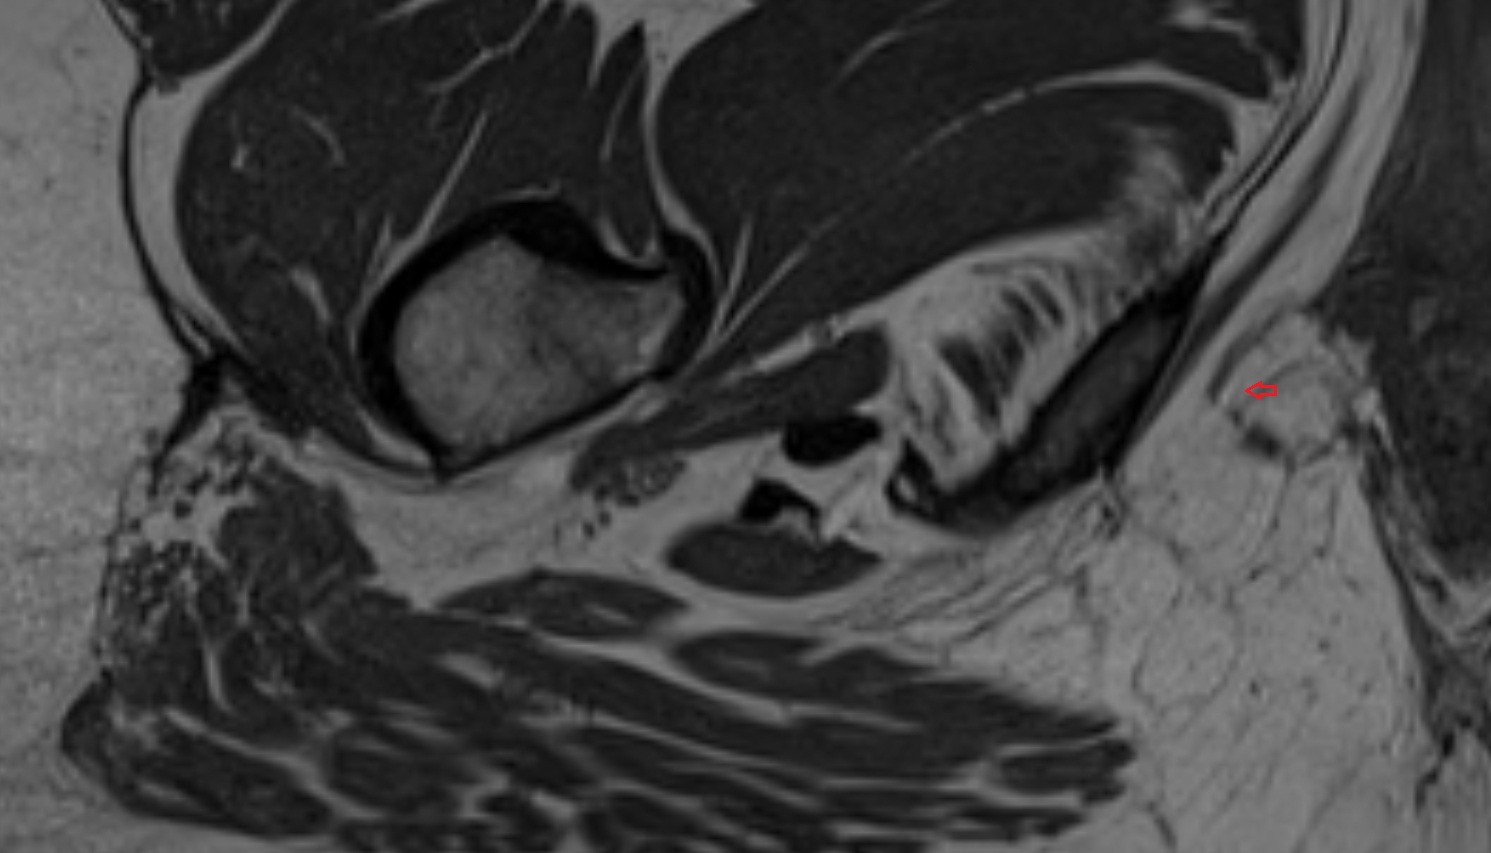

- Hip joint

- Head of femur

- Neck of femur

- Greater trochanter

- Ischial tuberosity

- Ramus of ischium

- Acetabular labrum

- Articular capsule of hip joint

- Obturator internus muscle

- Piriformis muscle